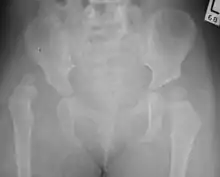

Hip dysplasia diagnosed by ultrasound[40] and projectional radiography ("X-ray").[41] Ultrasound imaging is generally preferred at up to 4 months due to limited ossification of the skeleton.[39][notes 1]

Despite the widespread of ultrasound, pelvis X-ray is still frequently used to diagnose or monitor hip dysplasia or for assessing other congenital conditions or bone tumors.[42] The most useful lines and angles that can be drawn in the pediatric pelvis assessing hip dysplasia are as follows:[42] Different measurements are used in adults.[42]